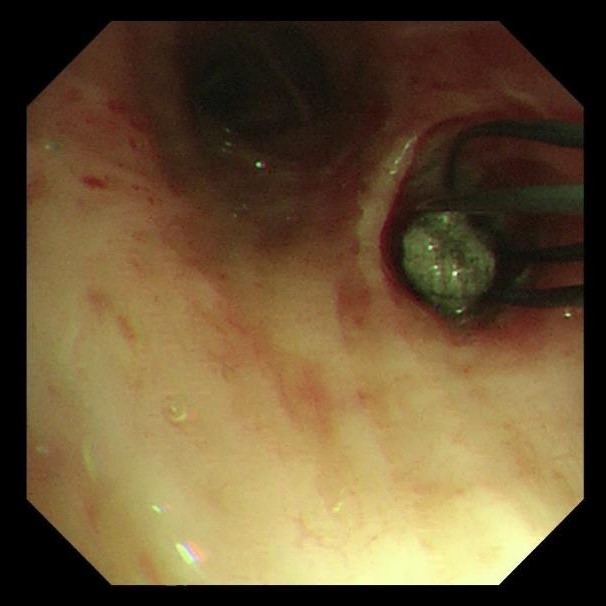

两天后复查支气管镜,发现患者左下叶背段远端细支气管仍有残留泥沙样异物。团队采用超细支气管镜联合冷冻技术,通过冷冻探头将异物凝固,再用超细活检钳逐支清理,实现对远端气道的彻底清理,实现气道“零死角”。

(远端支气管治疗后)